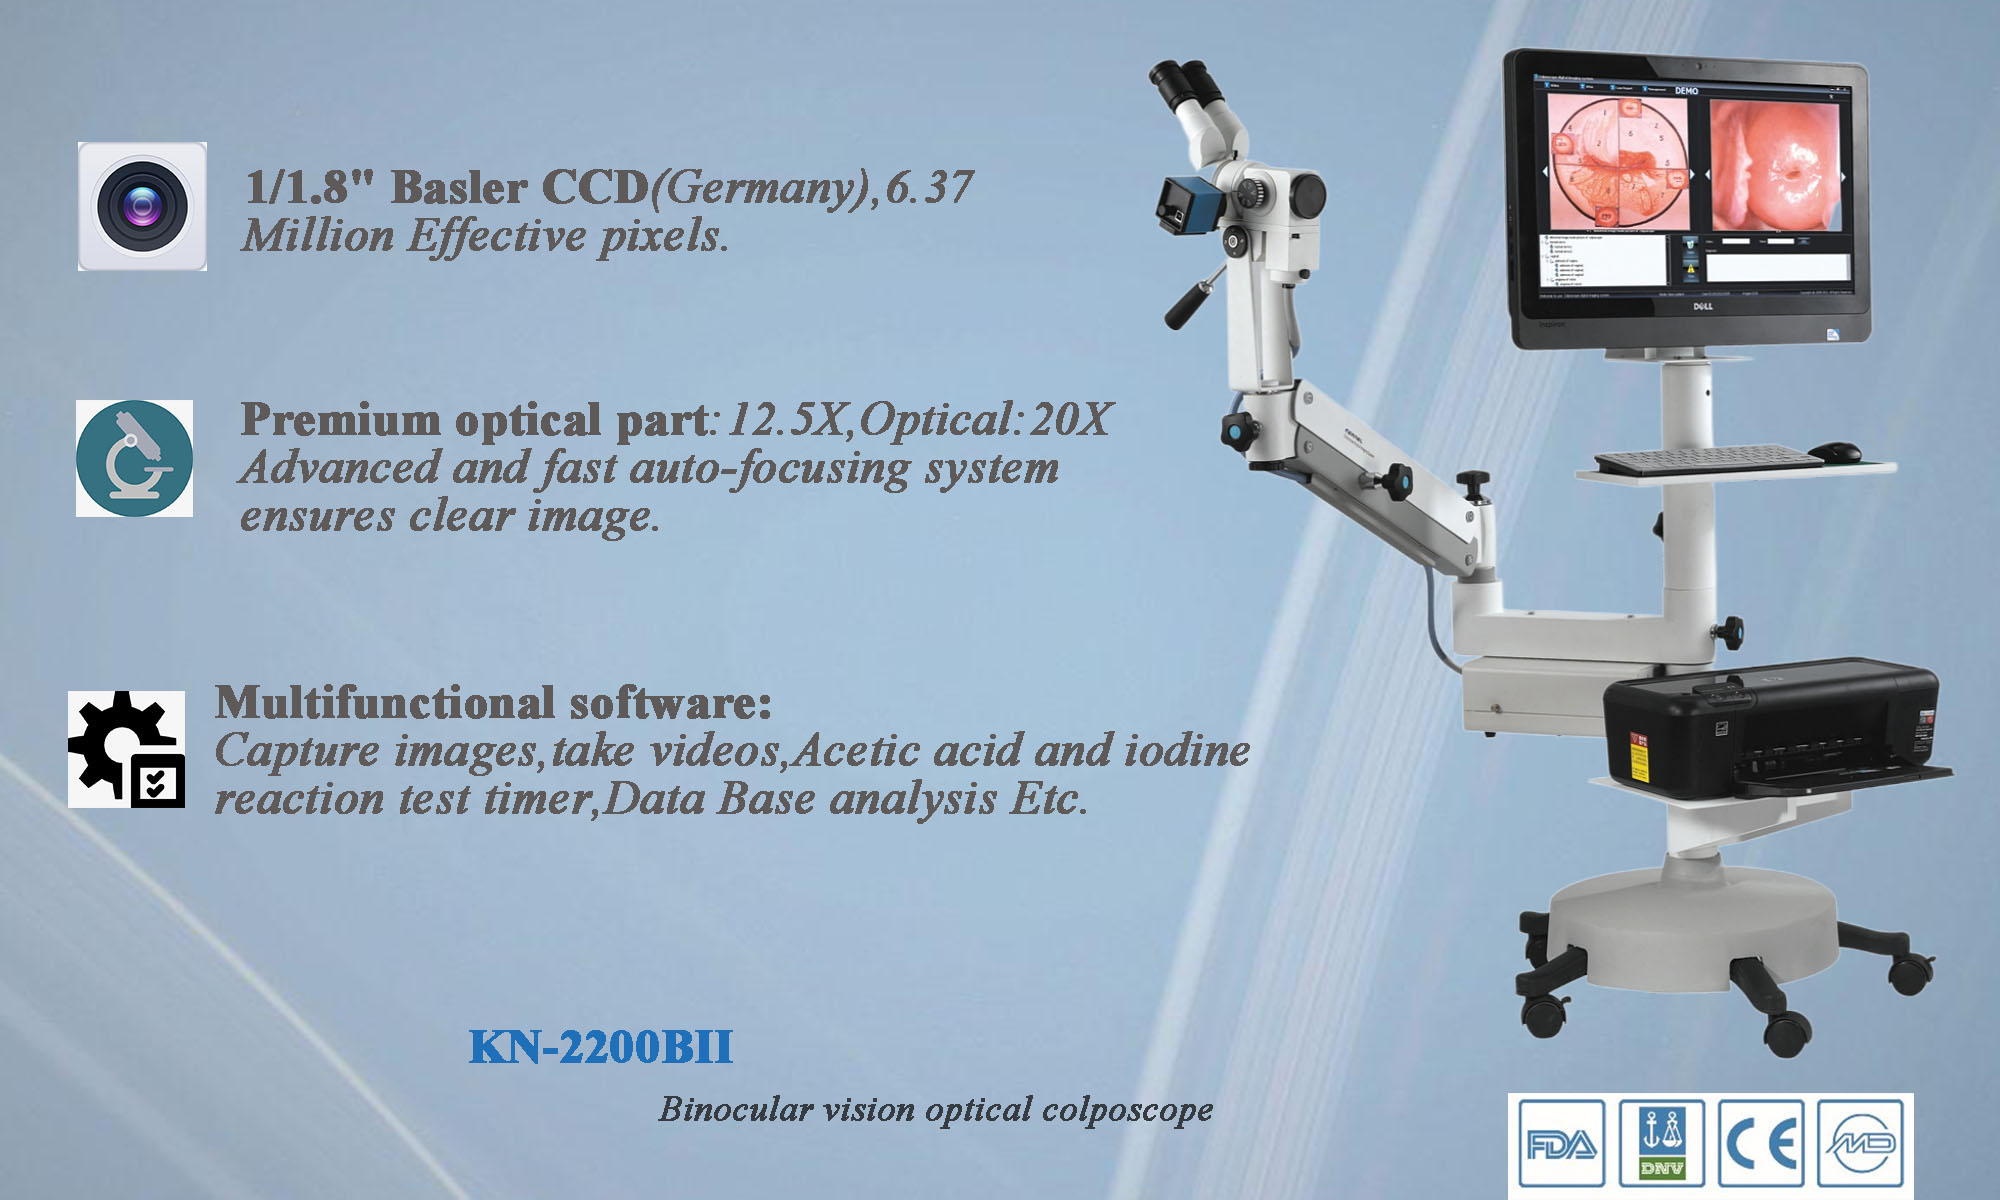

Kernel KN-2200BII CE Digital Video Colposcope with Management Software Digital Optical Electronic Colposcope

What Sets Kernel KN-2200BII apart from other video colposcope?

**Golden standard of Kernel kn2200 series,with superb German Basler camera 6.37 million effective pixels.

**Combining the advantages of microscope optical system and electronic colposcopy imaging system, it is the perfect combination of optics and electronics.

**Golden standard of this series,with superb German Basler camera 6.37 million effective pixels

**Extra long depth of field, super large field of view, super three-dimensional sense, realistic color reproduction, unique light path design, providing true 3D visual effects for pre-cancerous, pre-lesional punctiform vessels, columnar epithelium and some tiny lesions .

**50times System Magnification ,17 times optical amplication,3 times Digital amplification.able to output divine clear view of the examination lesion parts. Provide doctors with 3D visual image of the epithelial tissues,and different levels of the blood vessels. **LED light source,lifespan more than 20,000hours. **Horizontal Resolution up to 2064.